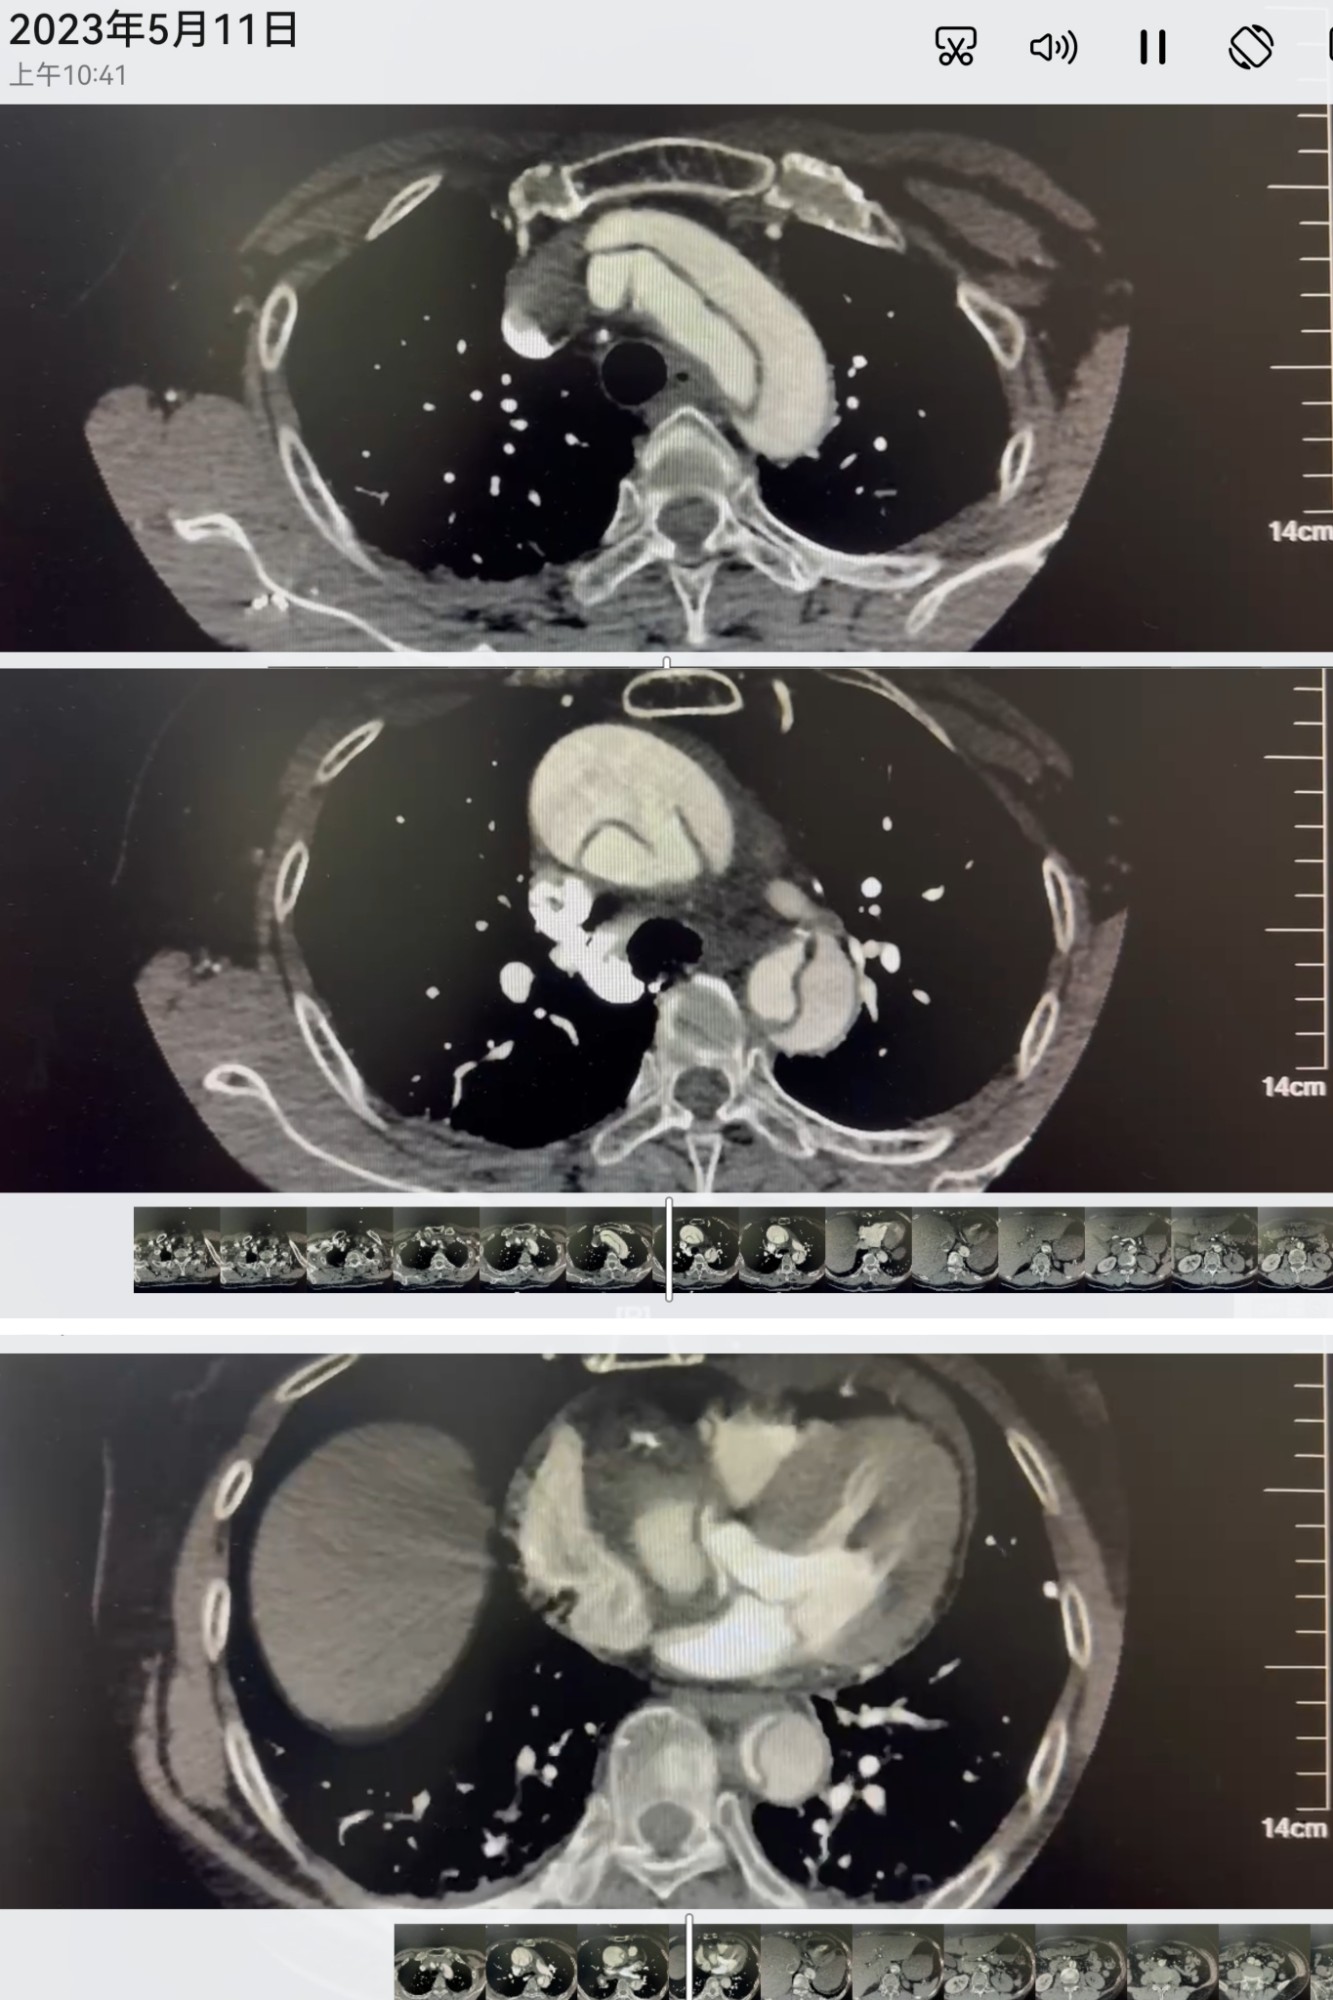

外院CTA影像

“患者送来医院的时候精神很差,伴有持续剧烈胸痛、难以忍受的症状,根据家属的病史表述,根据胸部CT平扫发现她主动脉增宽,不能排除主动脉夹层,随即完善主动脉CTA,当即就提示主动脉夹层、心包填塞,病情是非常危重的。” 潘禹辰表示。